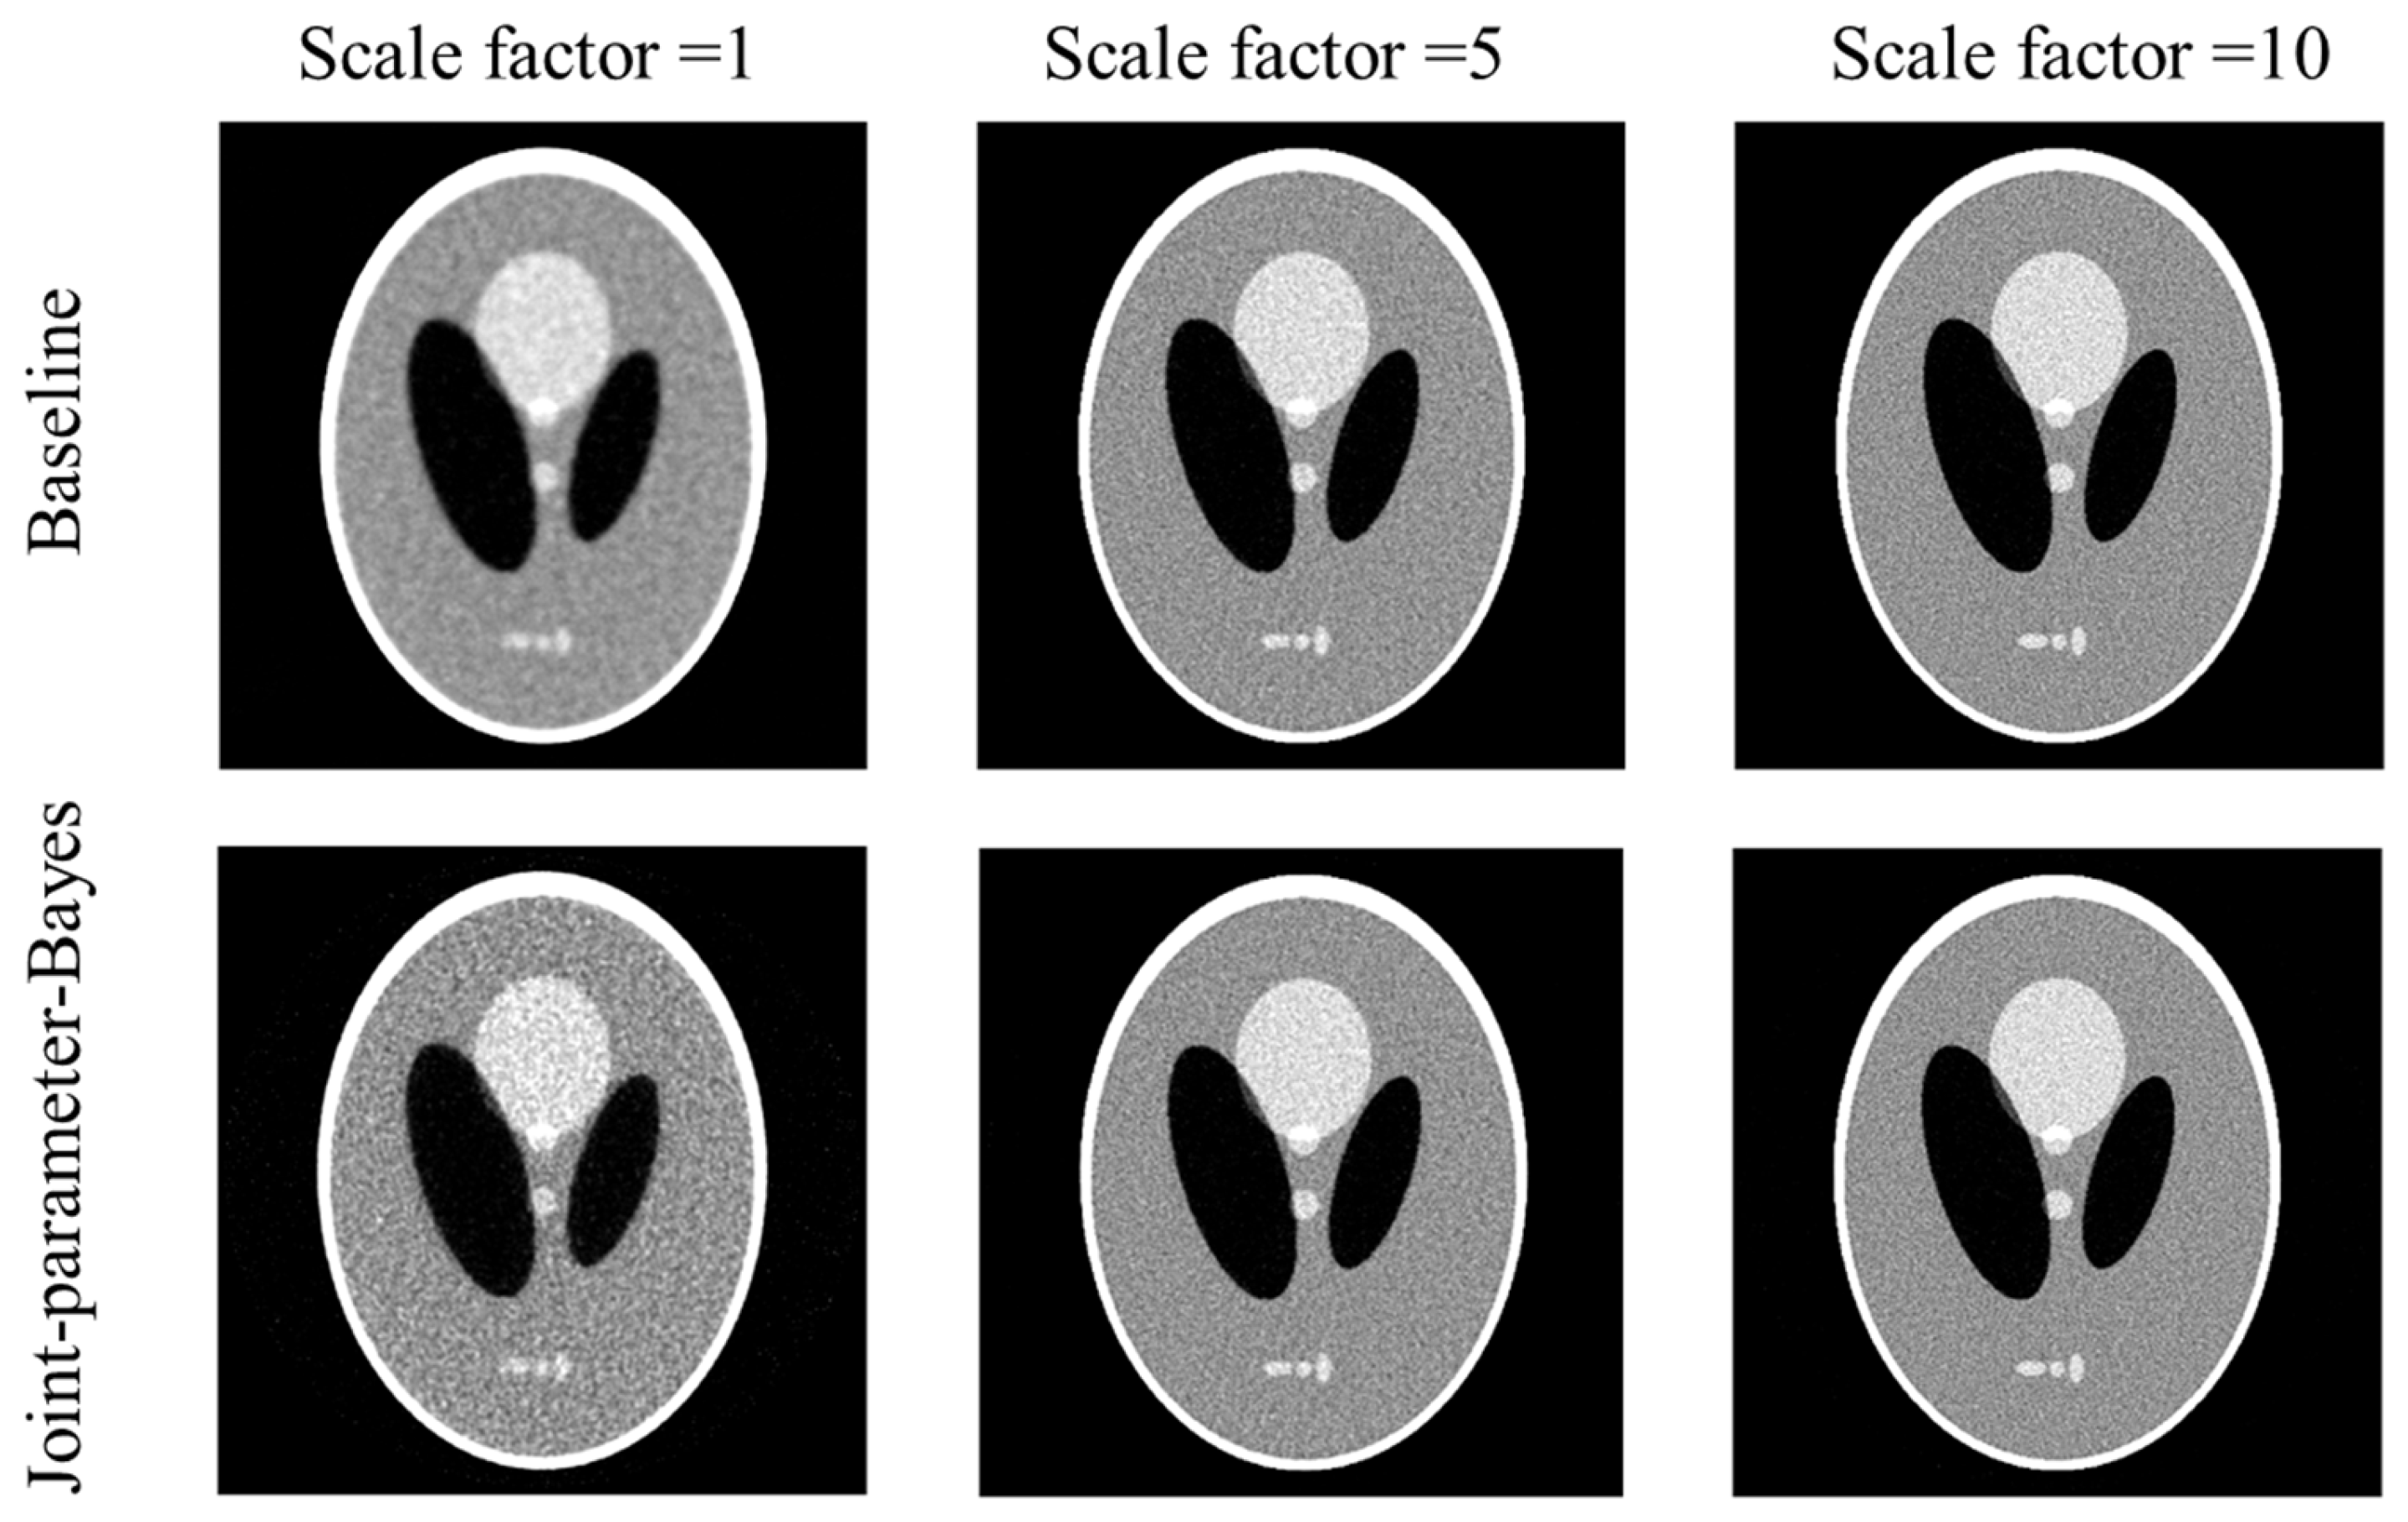

Figure 2 shows the reconstructed images both by the conventional MAP (baseline) and joint-parameter-Bayes with different noise levels. It can be observed that the results are comparable. The quantitative comparisons are summarized in Table 1 which are also consistent with our visual inspection. However, their computation time is quite different based on the iterations they use in Table 1. The proposed joint-parameter-Bayes saves approximately 66~88% of computation time in comparison with the baseline method. The number of iterations for joint-parameter-Bayes is further discussed in the stopping criterion subsection. To test the robustness, we performed the experiments on two other noise types: (1) Poisson-like signal-dependent noise to post-log sinogram data; (2) Poisson noise to the pre-log transmission data. We repeated the above evaluations and yielded very similar results, which can be found in the Appendix A. Some details of the two noise models are also be discussed in the following subsections.

Figure 2.

Comparison of reconstructed images between the conventional MAP (top row) and joint-parameter-Bayes (bottom row). The display window is [0, 0.035] mm−1.